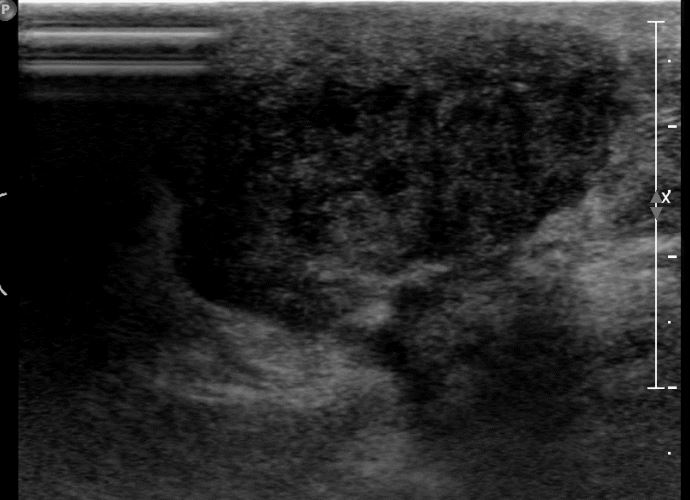

외부검사상 이상소견으로 내원하신 60대 여성분으로 우측 유방 조직검사 시행후

유방암 진단 되었읍니다.빠른 쾌유 바랍니다.